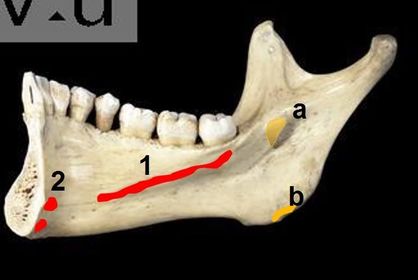

1) mention structure attached to 1 2) identify 2 3) structures attached to a and b 1) mylohyoid muscle 2) genial tubercles 3) a-sphenomadibular ligament b- Medial pterygoid muscle